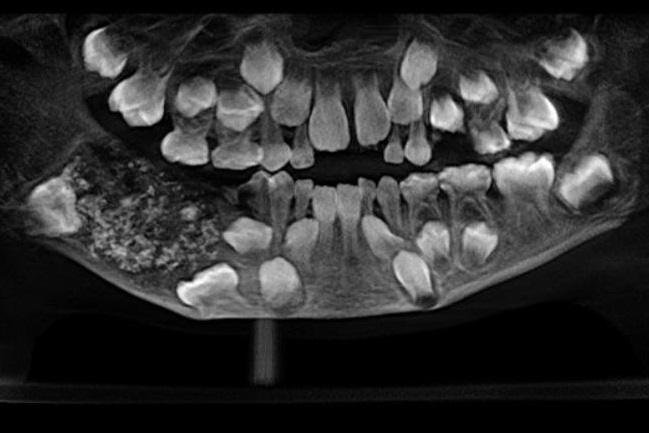

Un niño de siete años fue al dentista quejándose de un fuerte dolor de mandíbula, pero los médicos encontraron un raro caso: tenía 526 dientes "extra".

Luego de pedir que lo revisaran por el intenso dolor en sus muelas y mandíbula, le tomaron una radiografía, que mostró una especie de "saco" con varios dientes alojados en la parte baja de su boca.

Según informó CNN, los dientes "anormales" fueron extraídos el mes pasado, pero les tomó tiempo examinarlos y corroborar lo ocurrido. A los médicos les tomó más de cuatro horas revisar el "saco" y sus contenidos, confirmando el extraño hallazgo.

Las piezas dentales iban desde los 0.1 milímetros a 15 milímetros y todas tenían corona y raíz.

Los médicos detallaron que el niño sufrió una condición muy rara llamada odontoma, correspondiente a tumores benignos.